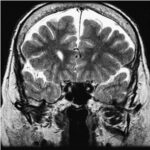

En primer lugar, se puede tratar el caso de los adictos al cannabis, cuya droga tiene efectos sobre el sistema endocannabinoide y en las áreas cerebrales vinculadas con la regulación de las emociones y el estrés. Un estudio de casos y control demostró mediante tomografía por emisión de positrones (PET) cómo la exposición crónica al cannabis, específicamente al THC, reduce la respuesta cerebral a la dopamina, y por ende, mayor puntuación de emocionalidad negativa en los adictos a esta sustancia respecto de los que no lo son. Esto se demostró con el uso de fármacos estimulantes, como el metilfenidato. Este mismo fenómeno también se ha observado con drogas como el alcohol, la cocaína y la nicotina. El cannabis también ocasiona una disminución en el metabolismo de la glucosa cerebral en el cuerpo estriado, tálamo y mesencéfalo(15) (ver Imagen 3).